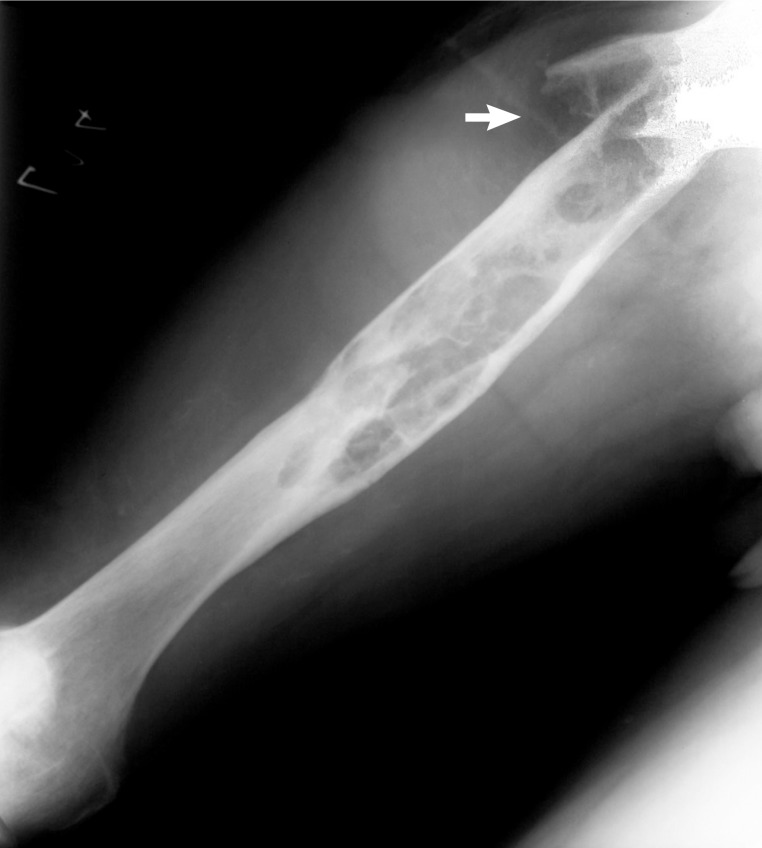

Skeletal Manifestations of Hydatid Disease in Serbia: Demographic Distribution, Site Involvement, Radiological Findings, and Complications

The Korean Journal of Parasitology 2013;51(4):453-459.